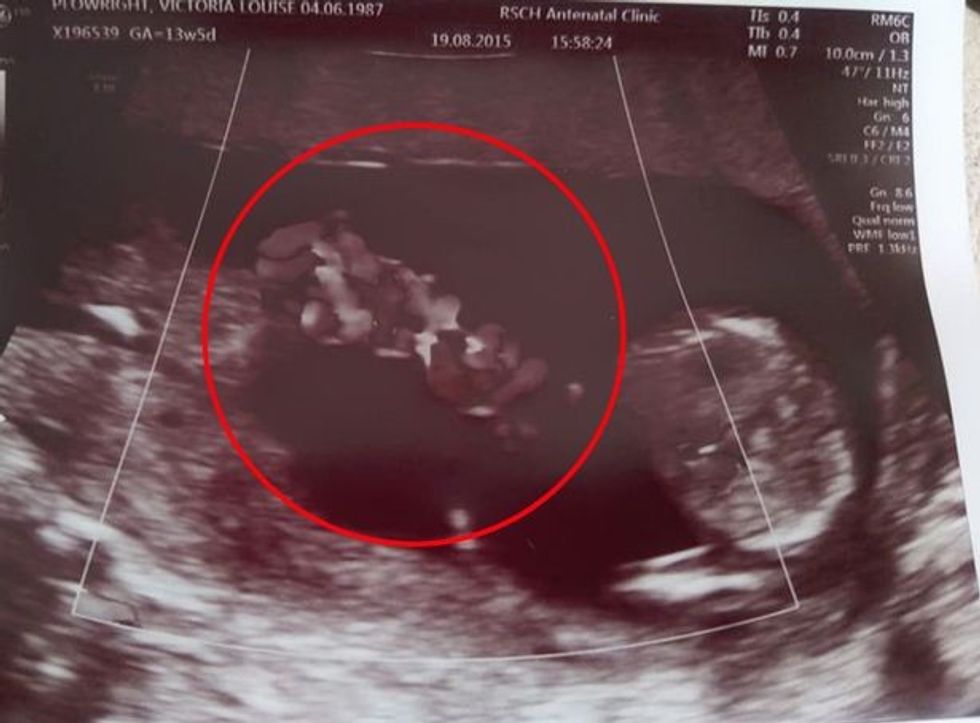

Sipas mediave të huaja, përcjell Telegrafi, bëhet fjalë për infermieren e fëmijëve Vicky Plowright, 30 vjeçe, së cilës i është thënë gjatë skenimit të saj 10-javor se binjakët ishin monoamnikë – domethënë ata ndanin një qeskë amniotike.

Por gjatë skanimit në javën e 12-të, një sonograf i tha Vicky se foshnjat e saj kishin lëvizur në një përqafim shpëtues.

Çuditërisht, pozita e tyre e ngushtë i ndaloi lidhjet e tyre të ngatërroheshin.